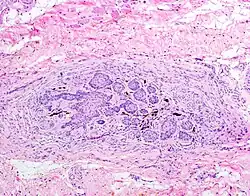

The juxtaoral organ of Chievitz is composed of nests of benign squamoid epithelium closely associated with multiple nerve bundles. The deep location and squamous appearance can histologically mimic invasive squamous cell carcinoma. (Hematoxylin and Eosin stained section, 100x magnification)

The juxtaoral organ in humans is a small longish structure (12.7 mm (half an inch) in length, 1–2  mm in diameter), situated medially to the medial pterygoid muscle. The organ consists of a central ramified cord of epithelial parenchyma, embedded in connective tissue particularly rich in nerve fibers and sensory receptors. Close relations exist between epithelial cells and nerve endings. Histochemically, the parenchyma displays a characteristic pattern of various enzymes. Sporadically, epithelial follicles containing colloidal material can be found. The organ is surrounded by a dense, perineurium-like connective tissue.